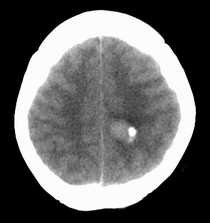

患者,女性,33岁,外伤检查发现,既往没有明显类似病史。

ct平扫见左侧脑室后角不规则形,边界不清的等密度肿块,肿瘤内有钙化,瘤周可见残存的脑室(低密度脑脊液影),考虑脉络脉丛乳头状瘤或室管膜瘤.

左侧侧脑室三角区占位性病变,其特点是平扫边界清、密度高、其内可见大块结节样的钙化,首先考虑起源于侧脑室三角区残余蛛网膜上皮的脑膜瘤可能性最大,无论是形态、密度、好发部位均符合脑膜瘤特点,建议增强进一步检查。

左侧脑室内软组织肿物,内部见多发不规则钙化,边界清楚锐利,有分叶。相应左侧脑室扩张。常见的不外乎3种病:室管膜瘤,脑膜瘤,脉络脉丛乳头状瘤。脑膜瘤分叶较少见,脉络脉丛乳头状瘤钙化较少见,因此,室管膜瘤可能性最大。

左侧脑室内见不规则略高密度团块影,边缘分叶,内见多发不规则钙化,病灶与侧脑室壁关系较为密切,左侧脑室扩大。考虑室管膜瘤可能性较大,其次为脑膜瘤,脉络丛乳头状瘤的可能性最小。

平扫见左侧脑室三角区不规则形肿块,肿瘤内有钙化,瘤周可见残存的脑室(低密度脑脊液影),考虑脉络脉丛乳头状瘤或室管膜瘤.

侧脑室三角区占位,首先考虑脑膜瘤,其次考虑室管膜瘤,室管膜瘤相对密度混杂一些,低一些。脉络丛乳头状瘤可能性不大,因为没有脑脊液明显增多改变,而且成人多在四脑室。

左侧侧脑室内分叶状肿块,其内见块状钙化,见左侧脑室阻塞性积水.考虑:脉络丛乳头状瘤

因病人无交通性脑积水,故脉络丛乳头状瘤不支持,脑室内脑膜瘤及室管膜瘤均有可能,病灶密度较高,前者可能性更大,建议结合增强检查。

左侧脑室后角不规则形,边界尚清的等密度肿块,肿瘤内有钙化。考虑脑膜瘤或室管膜瘤。

ct平扫见左侧脑室后角不规则形,边界不清的等密度肿块,肿瘤内有钙化,瘤周可见残存的脑室(低密度脑脊液影),考虑考虑脑膜瘤